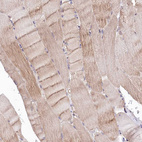

Immunohistochemical staining of human pancreas shows strong cytoplasmic granular positivity in exocrine glandular cells.